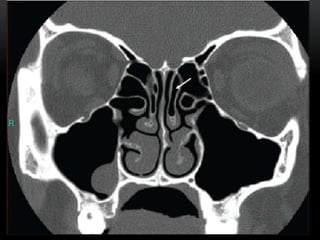

C – Cribiform plate (keros classification) – to assess the depth of olfactory fossa, length of lateral lamella, symmetry, slope or any dehiscence.

L – Lamina Papyracea – look for dehiscence, so if there is dehiscence make sure to be extra careful when using microdebrider around this area as incident such as injuring the orbital fat or rectus muscle could occur.

O – Onodi cell – if present, to assess its relationship to optic nerve, ICA, dehiscence (coronal and axial) and presence of horizontal septa.

S – Sphenoid sinus – pneumatization, septations, dehiscence of carotid artery or optic nerve.

S – Skull base – dehiscence, slope (examine sagittal plane of CT scan)

E – Ethmoidal artery position (skull base or pedicle), symmetrical? Usually anterior ethmoidal artery (~40% hanging )